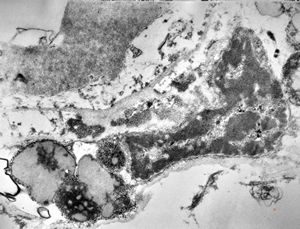

M,71y. | Alzheimer diseaseaccompanied with CADASIL

M,71y. | Alzheimer diseaseaccompanied with CADASIL

M,71y. | Alzheimer diseaseaccompanied with CADASIL

M,71y. | Alzheimer diseaseaccompanied with CADASIL - hyaline body in astrocyte

M,71y. | Alzheimer diseaseaccompanied with CADASIL - hyaline body in astrocyte

M,71y. | Alzheimer diseaseaccompanied with CADASIL - amyloid body

M,71y. | Alzheimer diseaseaccompanied with CADASIL - hyaline body in astrocyte